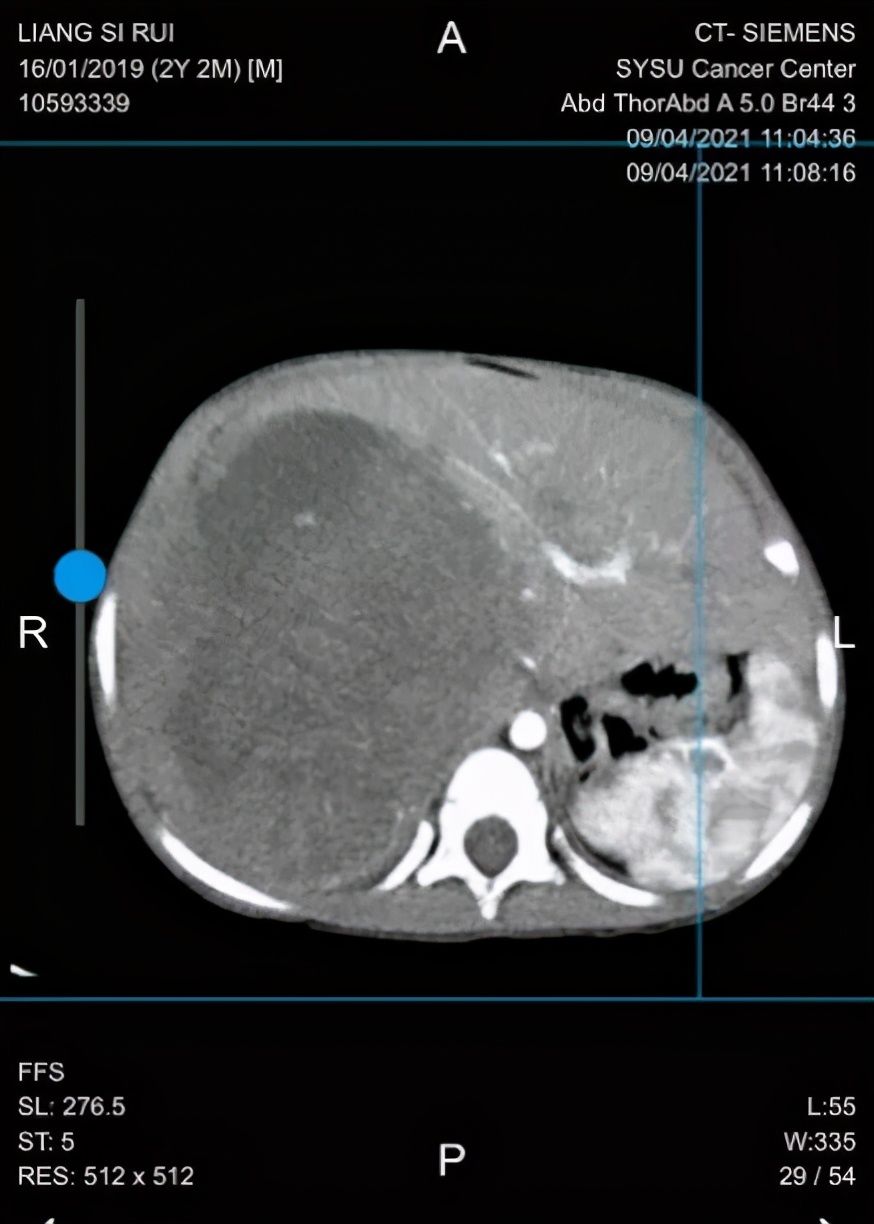

但在今年1月的复查中,欣欣的AFP再次升高,CT结果也是坏消息:肝里面的肿瘤复发了!心急如焚的家人带着欣欣辗转多地,最终慕名来到了中肿。儿童肿瘤科张翼鷟主任团队为欣欣量身定制了治疗方案,三程化疗后,肝脏中的肿瘤明显缩小,但如果想取得更好的治疗效果,手术是最佳选择。

随后,家长立即将孩子送到中肿就医,经全面检查,病理结果显示符合(混合型)肾母细胞瘤,CT检查提示肿瘤巨大、血供丰富,边界不清累及肝脏、肾脏和人体最大的静脉——下腔静脉。